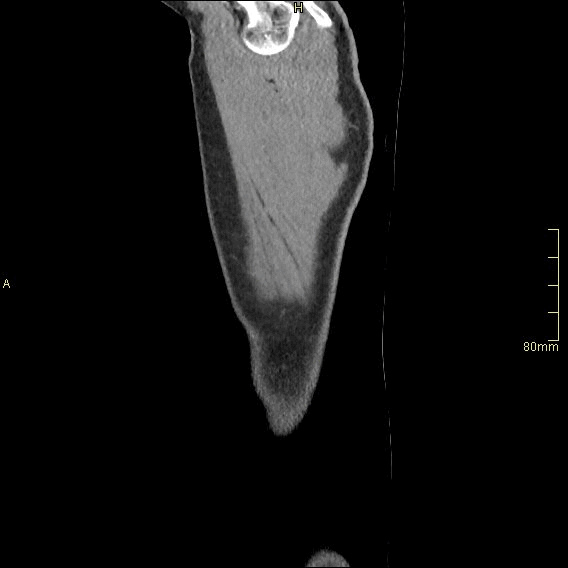

Example below is a General Chest/Abdo/Pelvis with contrast. Bony & Lung reconstructions are available depending on clinical question and differential diagnosis

Chest Arterial (Coronal)

Portal Venous Abdomen (Coronal)

Chest Arterial (Sagittal)

Portal Venous Abdomen (Sagittal)